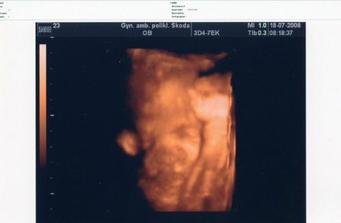

•••••••••• 16.4.2008 (19+5tt) výsledky z tripplů máme v pořádku, dostali jsme první 3D fotečku, jen nám paní doktorka nakonec nedělala screening ve 20tt, protože nám ho budou dělat v pondělí 21.4. v Praze (prý stačí jen jednou)